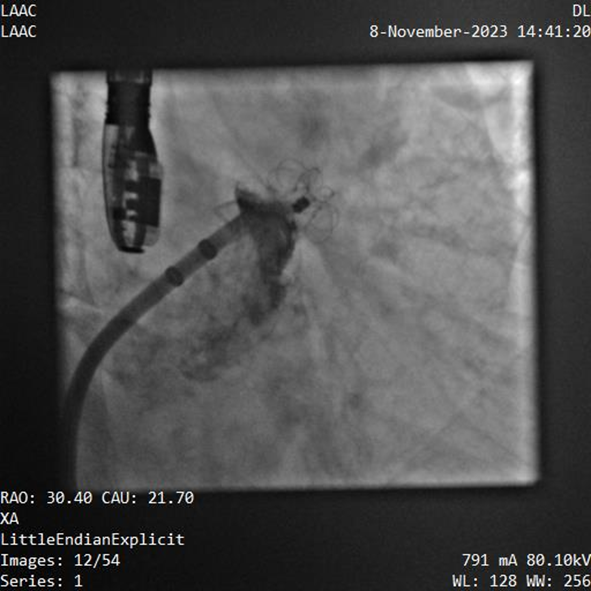

該例患者為男性58歲,陣發(fā)性房顫,9個月前突發(fā)急性腦梗死,3月前曾行房顫射頻消融術(shù)。2023年11月經(jīng)胸超聲心動圖示左房內(nèi)徑46mm,經(jīng)食道超聲心動圖示左心房及左心耳內(nèi)未見血栓形成,CHA2DS2-VASc評分3分,HAS-BLED評分2分。DSA測得左心耳開口直徑約23mm,錨定區(qū)域約18mm。

葛均波院士、周達(dá)新教授等經(jīng)詳細(xì)評估和討論后,認(rèn)為該受試者需要植入固定部20mm、封堵盤28mm的左心耳封堵器,為非常規(guī)固配規(guī)格,SimuLock的可選配組裝式設(shè)計精準(zhǔn)滿足患者需求。

手術(shù)過程順利,通過植入非常規(guī)固配規(guī)格的固定部20mm、封堵盤28mm的左心耳封堵器,實(shí)現(xiàn)左心耳完全封堵,達(dá)到手術(shù)預(yù)期效果,再次體現(xiàn)產(chǎn)品獨(dú)特的設(shè)計創(chuàng)新優(yōu)勢。

器械釋放后造影示封堵器展開良好,封堵完全